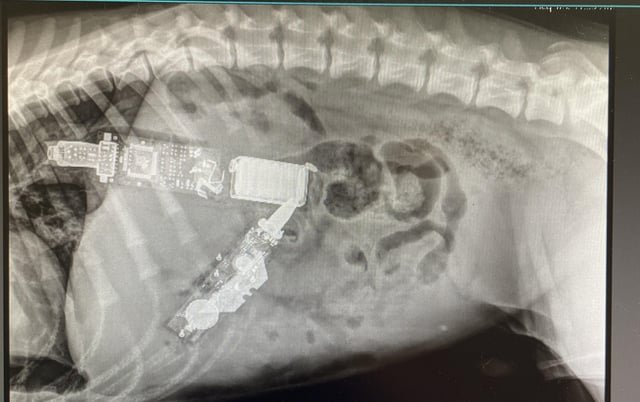

Unfortunately, the owners elected to euthanize due to complicating factors. My coworkers and I are stumped.